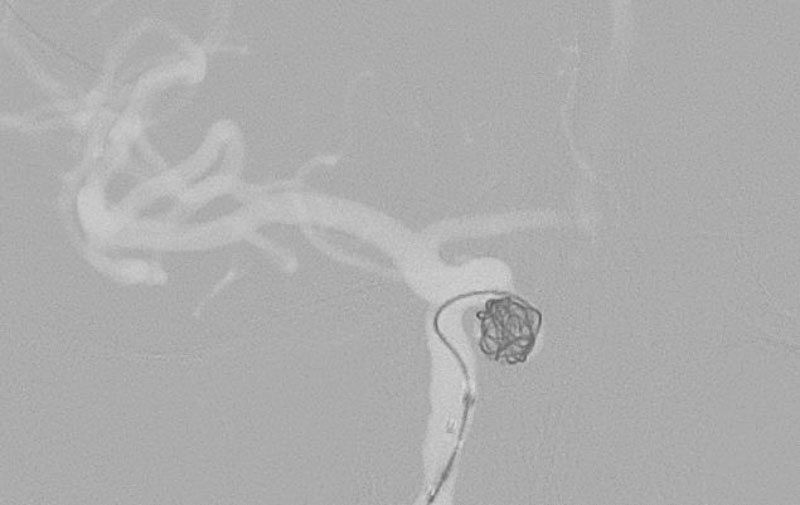

No.1596 手術中